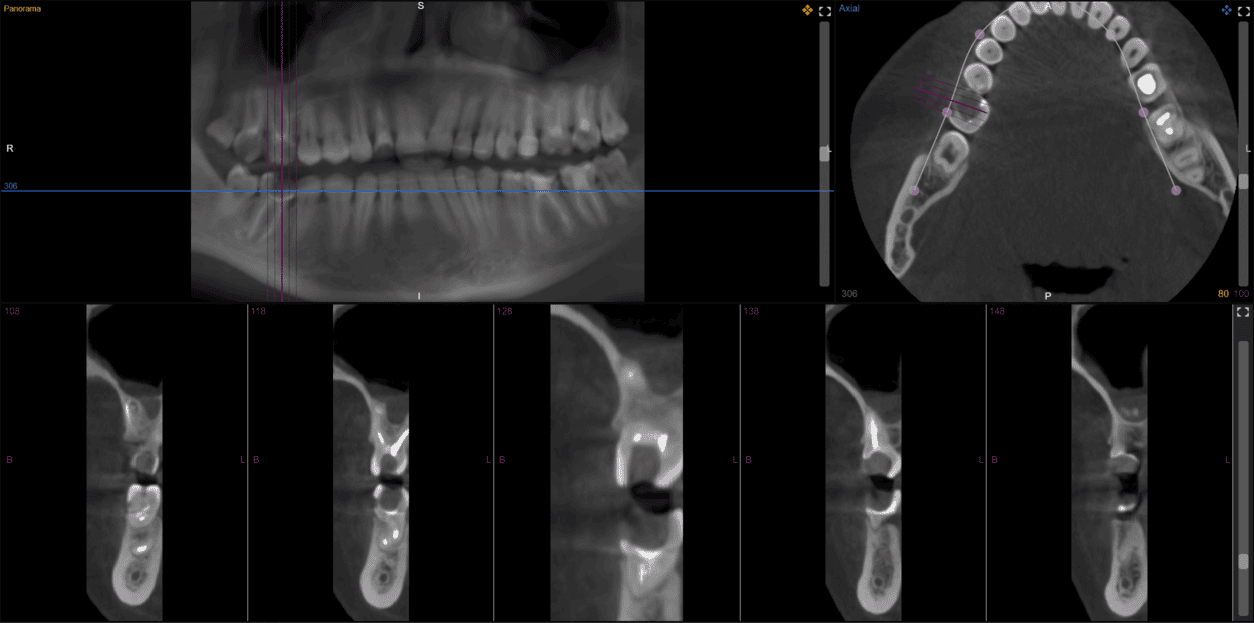

Any CT scans

Different devices